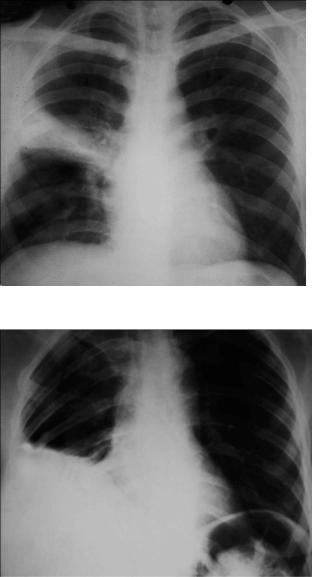

Рентгенологический признак пневмонии – инфильтративное, обычно одностороннее затемнение легочной ткани, которое может быть очаговым, сливным, сегментарным (рис.1-2), долевым (обычно гомогенным) и тотальным. Рентгенологическое исследование следует проводить в двух проекциях – задне-передней и боковой. При выполнении исследования следует оценить распространенность инфильтрации, наличие или отсутствие плеврального выпота и полости деструкции.

Плевральный выпот осложняет течение ВП в 10-25% случаев и не имеет особого значения в предсказании этиологии заболевания (рис. 1-3).

Рис. 1-2. Внебольничная сегментарная пневмония с локализацией в верхней доле правого легкого.

Рис.1-3. Внебольничная пневмония, осложненная экссудативным плевритом.